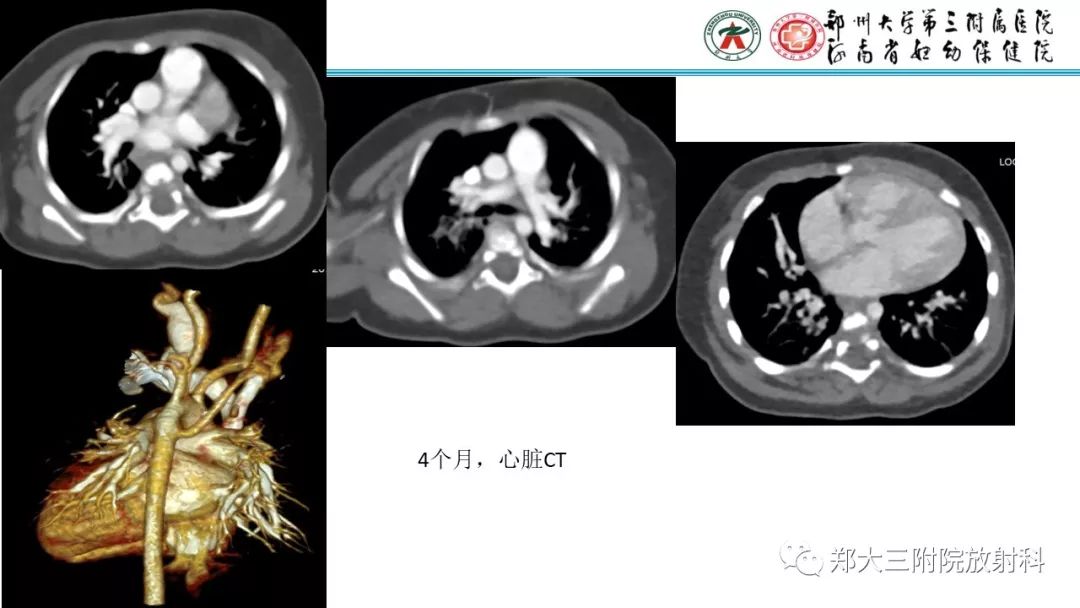

DiGeorge迪格奥尔格综合征1例CT